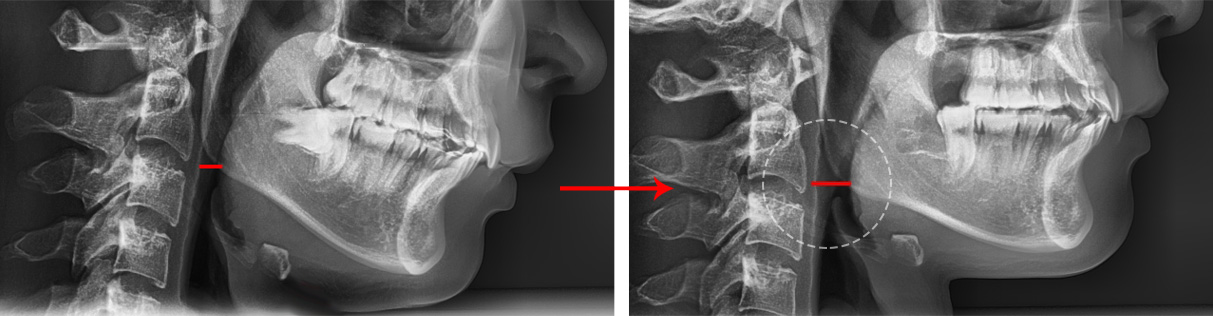

악궁 확장을 하게 되면 기도가 넓어지고 혀가 있을 공간이 충분히 확보되기 때문에

호흡이 편해져서 건강한 교정을 할 수 있습니다.

또한 아래턱이 움직일 수 있는 충분한 공간을 확보할 수 있기 때문에 안면 비대칭이 좋아지고

개방 교합도 개선되는 효과를 볼 수 있습니다. 좁아진 악궁을 확장시켜